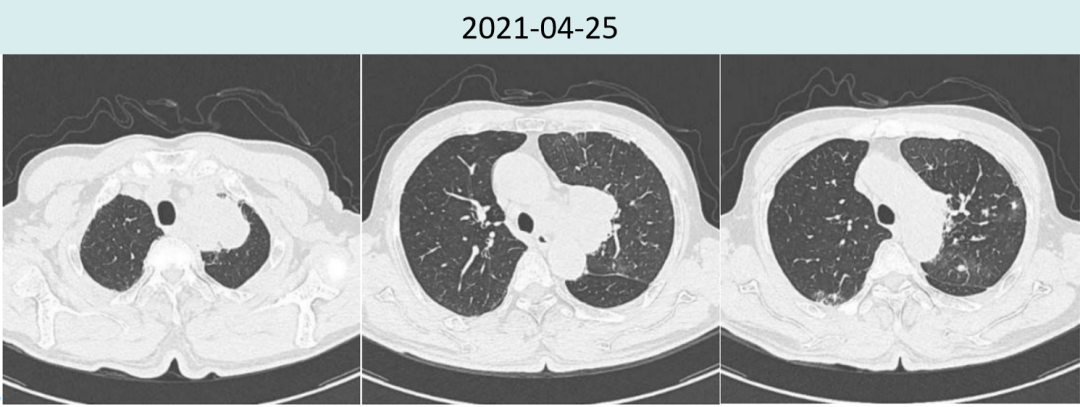

2021年4月25日胸部CT提示:左上肺占位,左肺?增?,考虑左上肺癌伴左肺?及纵隔淋巴结转移,两肺散在炎症,左肺上叶部分实变。左肺下叶磨玻璃结节。

2021年6月18日治疗两周期后复查胸部CT提示:肿瘤较前明显缩小(4.5cm→2.0cm),新增多发炎性病灶,总体疗效评价为PR。

图1.患者治疗前后胸部病灶对比